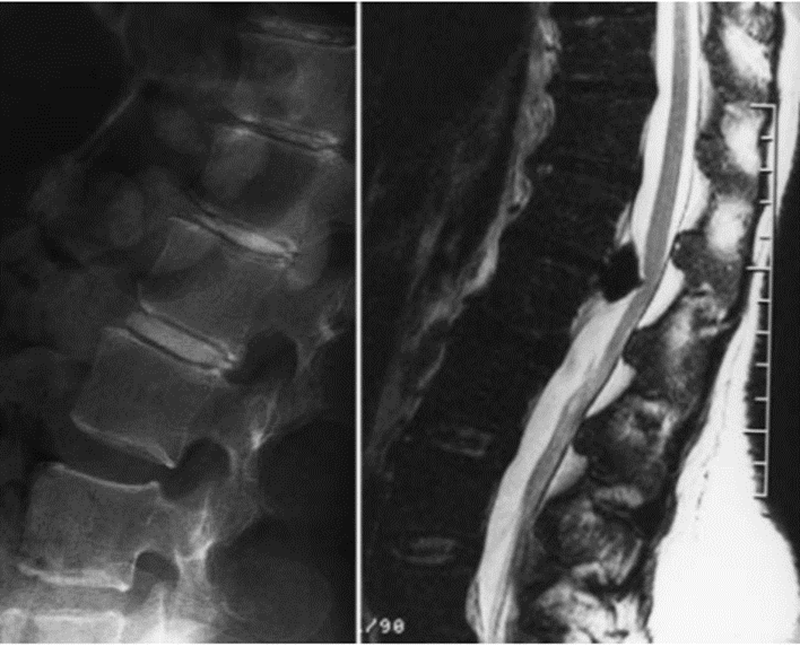

焦磷酸钙沉积疾病引起炎症性背痛

焦磷酸钙沉积疾病伪装成脊髓感染

腰椎MRI,L2和L3椎体强化,骨髓水肿,伴椎前/椎旁软组织肿胀,弥漫性椎间盘膨出,黄韧带增厚,椎管狭窄

腰椎MRI,L2/3明显狭窄,左侧明显,伴椎间盘炎和中度硬膜囊压迫,周围可见软组织水肿,左侧腰大肌轻度水肿。